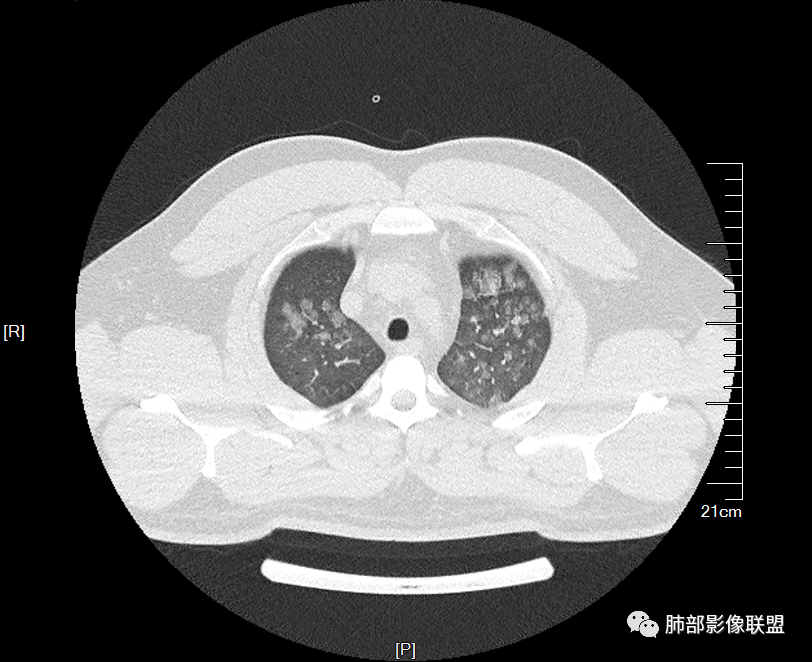

双肺多发弥漫性磨玻璃结节影,大小不一,形态不规则,部分融合,支气管未见明显扩张,部分血管束略增粗,叶裂胸膜增厚,临床有痛风,左足痛6天,考虑:1:痛风结节(一般实性结节,很少磨玻璃结节影)2:血管炎?3:病毒性肺炎(水痘-疱疹肺炎?)

双肺多发腺泡结节及磨玻璃,小叶间隔增厚(大网格状),腺泡结节内及磨玻璃内可见细网格影(小叶内间隔增厚),影像表现符合肺泡出血改变,血肌酐升高,考虑肺肾综合征。鉴别肺水肿。

两肺弥漫向心分布的腺泡结节,部分融合,两肺小叶间隔增厚,血肌肝高,考虑肺泡性肺水肿

青年男性,痛风、肾功能不全病史,双肺多发结节状、斑片状阴影,支气管血管束增粗,可见支气管袖口征,叶间裂及小叶间隔增厚,考虑肺水肿。

年轻男性,既往血肌酐升高,左足痛六天入院,有痛风及高血压病史。CT示双肺多发磨玻璃结节影,不规则,部分融合成团或片状,小叶间隔增厚,以双下肺为明显,叶间胸膜亦见增厚。考虑为1.Good-Pasture综合征。2.病毒性肺炎?3.肺水肿?

男32岁。既往曾发现血肌酐升高.此次因左足痛6天入院。有痛风、高血压病史。两肺弥漫性的病变,小片状或者结节状为主病变,小叶中心分部为主,边界不清。心影比较饱满,肝实质密度均匀的降低。考虑为肝损害的影像学改变。综合考虑多功能脏器的损害,肺部损害肺泡炎?肺水肿?或病毒性的肺炎?

年轻男性,有痛风、高血压病史,有肾功不全史。双肺弥漫性分布磨玻璃样结节,部分融合,无重力分布,考虑1.血管炎。2.肺肾综合征。3.肺水肿。

年轻男性,痛风史,高血压史,肌酐高,左足痛6天入院。胸CT:双肺多发弥漫性磨玻璃结节影,大小不一,部分融合,上中下肺都有,中内带多,胸膜下少。部分血管束略增粗,小叶内间隔、小叶间隔增厚,下肺明显,左室大。叶裂胸膜增厚。临床有痛风,左足痛6天,考虑:心衰、间质性肺水肿?弥漫性肺泡出血?鉴别:MPA,肺肾综合征,痛风结节等。

青年男性,有肾功能不全史和痛风史,这个影像分布有个典型的特点,全部是以中央间质周围的渗出性改变,这个改变主要就是两种可能,一种是肾功能不全导致的血管通透性增高导致的肾性肺水肿,一种是出血导致的DAH改变,具体是哪种,影像上不好简单的鉴别,需要结合更多临床资料综合分析。

年轻男性,痛风,肌酐高,提示肾功能有损,两肺多发磨玻璃腺泡结节,小叶间隔增厚,双侧少许胸水,血管增粗,考虑肾性肺水肿,DAD,鉴别肺肾综合征,需要更多临床资料

双肺多发腺泡结节及斑片状磨玻璃影,边缘不清,后者内见细网格状改变,小叶间隔增厚,呼吸系统症状不明显,考虑肺水肿,过敏性肺泡炎代排

32岁男性,左足痛入院。有痛风、肌酐升高、高血压病史。CT:两肺弥漫磨玻璃结节,小叶间隔增厚、小叶内间质增厚,两侧少量胸水。考虑:1.肺水肿;2.过敏性肺炎;3.肿瘤?

双肺多发腺泡结节及磨玻璃网格影,部分融合,小叶间隔增厚,双肺中轴间质增厚不明显,疾病谱:病毒性肺炎,肺泡出血,水肿,过敏性,肺泡蛋白沉着症,PCP。结合病史,没有咳血,肺泡出血,不考虑,过敏没有任何临床症状,而且无上肺分布优势,也排除。病毒性肺炎也无临床支持,排除。PAP影像不典型,暂排除。有肾功能异常,所以考虑1肾源性肺水肿。2,有无激素使用史或HIV,PCP待排。

青年男性,双肺多发大小不等斑片状磨玻璃密度影,内见细网格影,并可见小叶间隔增厚,双侧胸腔少量积液,患者曾有血肌酐增高,提示曾有肾损害,并有痛风、高血压病史,考虑肺肾综合征,鉴别过敏性肺炎

多发GGO结节,边界清,以全小叶、小叶中心为主:

GGO背景

小叶间隔增厚,无明显重力趋势

少量积液,脂肪肝

这里有一点重力趋势

中轴间质稍增厚

细网格也明显

中轴间质增厚,小叶间隔增厚,小叶内间质增厚,部分重力作用,双侧对称,胸水,按理淋巴道回流受阻有

肺水肿类病变有

问题是腺泡结节如何解释?